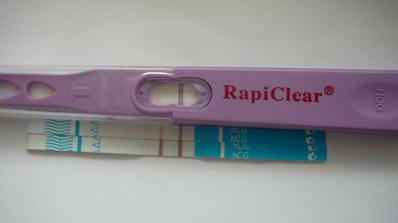

4.8. 2010 pozitivní tt